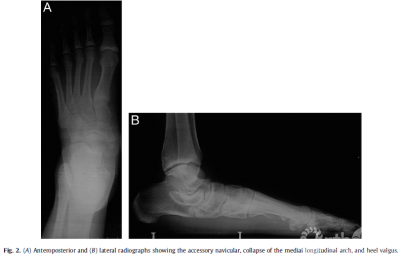

Patients and Methods From December 2008 to July2011, 16 patients (21 feet) with flexible flatfoot,symptomatic AN, and heelvalgus (Fig. 1) underwent MDCO with reconstruction of the PTT on the dorsalnavicular after excision of the AN. All cases were performed by 1 seniorsurgeon at the same hospital. The series consisted of 5 male and 11 female patients,with a mean age of 41.5 years (range 18 to 64years). Of the 16 patients, 11 hadunilateral flatfeet and 5 bilateral flatfeet. All patients had flexibleflatfoot symptoms with a symptomatic AN. The patients presented with chroniclocalized pain on the affected side that made it difficult for them to wearshoes. The presence of flexible flatfoot, AN, and heel valgus were proved radiographically(Fig. 2). Also, T1weighted fat suppressed magnetic resonance imaging showedthat the PTT was abnormally inserted on the AN.

Results The16patients (21 feet)were followed up for a mean duration of 28.5 months (range18 to 48). All patients were satisfied with their clinical results andwere abletowalk long distanceswithout any pain 6 months after surgery. No cases of woundinfection or nerve injury developed.The mean AOFAS ankle and hindfoot scoreshad improved from 53.3±6.5preoperatively to 90.8±1.4 at the last postoperativeassessment(p<.01; Table 1). The improvement in all radiographic parameters wasstatistically significant between the preoperative and last follow·up assessments(p < .01; Table 2). These changes provided evidence of recovery of the archheight and correction of heel valgus (Fig. 3). The foot appearance alsosuggested satisfactory outcomes (Fig. 4).